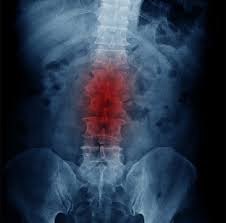

Smoking and degenerative disc disease. Research suggests that smokers are at a 3-4 times higher risk of developing degenerative disc disease and that smoking can exacerbate pre-existing disc degeneration. In time we all experience various levels of disc. Smoking and intervertebral disc degeneration.

Many things can be done to lower the risk or progression of DDD. New research from the Association of Academic Physiatrists has found smoking worsens degenerative disc disease in the spine. Whilst smoking has previously been connected with lumbar degeneration this study has associated it with degeneration of the cervical spine.

If you need another reason to quit smoking has now been linked to worsening degenerative disc disease. The Link Between Cigarette Smoking and Degenerative Disc Disease Smoking Is a Leading Risk Factor for DDD.